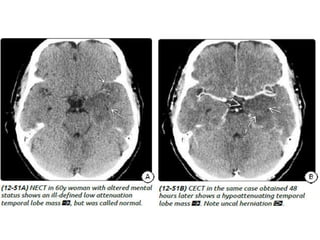

General Features- The "gold standard" for the diagnosis of bacterial

meningitis is CSF analysis.

Remember: Imaging is neither sensitive nor specific for the detection of

meningitis!